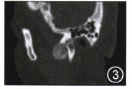

CT:右顳下頜關(guān)節(jié)有一不規(guī)則鈣化高密度灶,呈啞鈴形。外側(cè)部分類似球形,突破關(guān)節(jié)腔位于顴弓下方、乙狀切跡外側(cè)及髁突前方;中間部分沿關(guān)節(jié)腔分布,呈盤狀,與關(guān)節(jié)面間有潛在間隙,患例關(guān)節(jié)腔較健側(cè)明顯增寬;內(nèi)側(cè)部分跨越關(guān)節(jié)結(jié)節(jié)向前內(nèi)斜形進(jìn)入顳骨鱗部和蝶骨巖部,顱底骨質(zhì)破壞(圖1~3)。

圖1CT可見病灶突出關(guān)節(jié)腔內(nèi)外側(cè)呈球狀生長;圖2顳下頜關(guān)節(jié)間隙不均一的高密度盤狀鈣化影,鈣化影與髁突之間可見潛在間隙,病灶沿關(guān)節(jié)間隙分布,并向間隙內(nèi)及外突出;圖3病灶向前內(nèi)突出至顳下窩.鈣化物超越關(guān)節(jié)腔向外突出至面部,向內(nèi)擴(kuò)展至顱底;